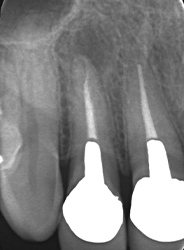

割れている

治療前

治療後

| 主訴 | 上の歯ぐきが腫れて痛かったので歯医者に行ったが、根が割れているので抜歯と言われたが、本当かどうか見てほしい |

|---|---|

| 施術内容 | 保存治療 |

| 治療期間 | 2ヵ月 |

| 費用 | 保存治療:138,000円 相談料:44,000円 |